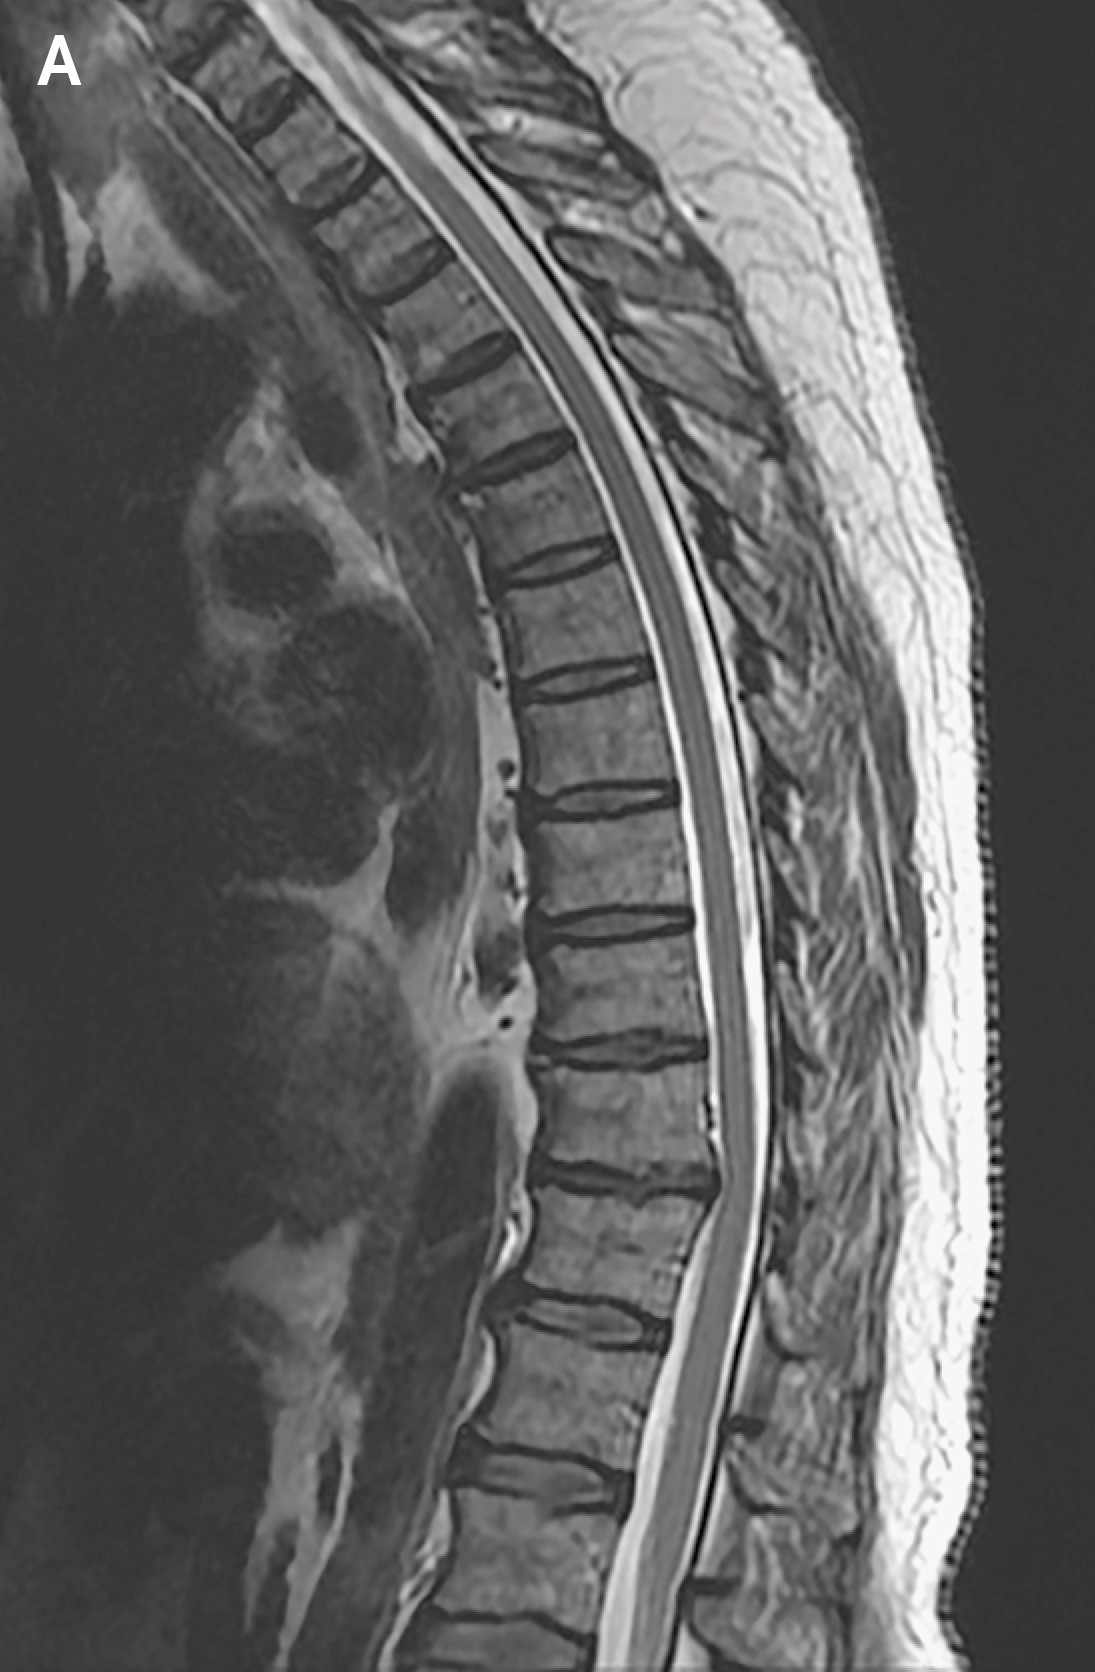

It is not uncommon during the summer and fall months in New England to make a diagnosis of Lyme polyradiculitis or meningoradiculitis in a patient who presents with a syndrome of subacute, multifocal, painful radiculitis. The syndrome typically affects the arms and legs in an asymmetric fashion and is often associated with cranial nerve palsies. Read the latest Case Records of the Massachusetts General Hospital here.